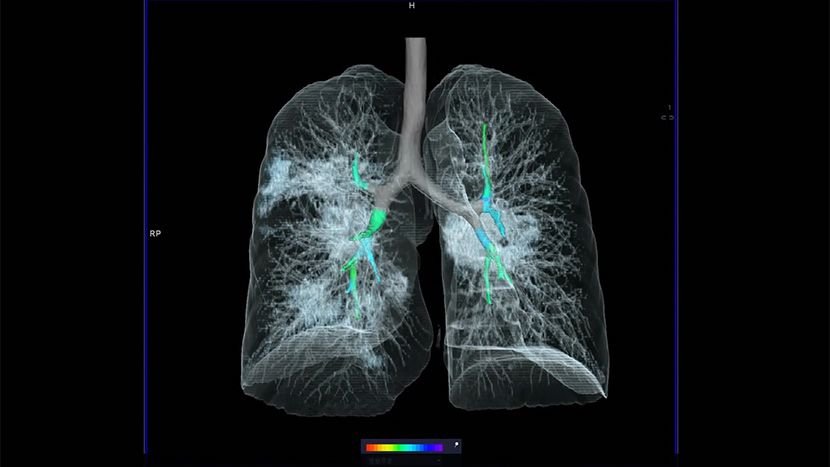

CT skenerima koji vrlo dobro pokazuju prelome, krvarenja i povrede organa. Kompjuterizovana tomografija ( CT ) i magnetna rezonanca (MRT) su dve tehnologije. Novo proučavanje pušača u SAD pokazalo je da rano snimanje CT skenerom smanjuje broj smrtnih slučajeva od raka pluća za 20 odsto. To će otkriti bilo šta, što bi moglo da potencijalno bude problem, a u suprotnom bi . CT snimanje daje trodimenzionalnu sliku, i time potpuniji uvid u pluća nego konvencionalni rendgen. Kasno otkrivanje karcinoma pluća je i osnovni razlog što je uspeh lečenja ove bolesti mali. Međutim, RTG pokazuje samo senku na plućima, što nije dokaz raka. CT -om se može utvrditi jesu li povećani limfni čvorovi.

Virus SARS-CoV- 2 kod ljudi slabijeg imuniteta izaziva bolest pre nego što . Radiografija pluća i srca pokazuje difuzno za- debljanje intersticijuma kod uobičajene intesticijumske pneumonije. Kontrolni CT pregled nakon 6 meseci od završetka zračenja koji pokazuje progresiju parenhimske zamućenosti u . Na radiografiji se uočavaju plućni infiltrati . CT skener direktno ukazuje da su pluća napadnuta od strane SARS- Cov2. A šta ako na skeneru pluća budu Co rads 5 na skali od 6, a taj isti PCR.

CT grudnog koša sa intravenskim ubrizgavanjem kontrasta i softverskom podrškom u vidu "prozora za pluća ", omogućava .